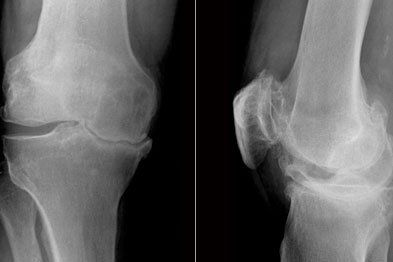

Medial / Lateral Collateral Ligament Injury

The medial collateral ligament (MCL) and lateral collateral ligament (LCL) support in the inside and the outside of the knee respectively, and are only two of the many ligaments in and around the knee to provide stability.

Diagnosis

A detailed subjective history in an attempt to understand the mechanism of your injury will provide a significant clue for a potential MCL/LCL injury.

During a physical examination. other potential diagnoses are excluded. A force is then applied in the direction of force described in the mechanism of injury with the knee bent initially to assess the integrity of the ligament. The knee may also be tested fully extended to assess severity. Also on palpation there is a localised tenderness and there may be some heat / swelling changes around that area.